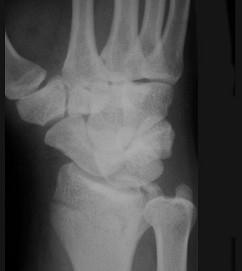

问题 男,22岁,滑冰时摔倒右手撑地时受伤,请结合CR片,选出最可能的诊断 ( )

选项 A、桡骨远端骨折 B、反柯莱斯骨折 C、蒙泰贾骨折 D、加莱阿齐骨折 E、柯莱斯骨折

答案 A